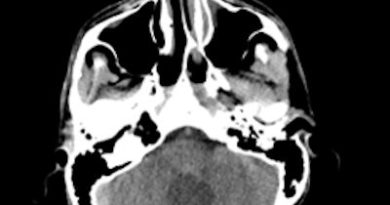

- A) Aksiyel BT görüntüde; temporal kemik petröz parçasında düzensizlikler (mor ok), petröz parçası posteriorunda heterojen iç yapıda hipo / hiperdens alanlar içeren kitlesel lezyon (turuncu ok) mevcuttur. DSA görüntüde, multiple besleyici arterleri olan hipervasküler kitle lezyonu (açık yeşil ok) demontre edilmektedir.

- BT’de, temporal kemiğin petröz parçasında infiltratif veya güve yeniği paterninde erozyon, petröz kemik posterioruna uzanan santral spiküle veya periferal rim tarzında kalsifikasyon içeren heterojen iç yapıda kitle lezyonu izlenebilir.